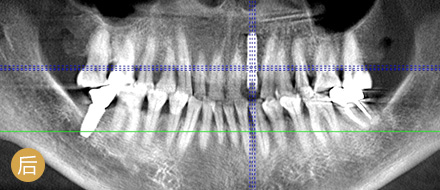

数字化精确导航种植

导航辅助种牙,创口小更舒服

• >智能导航,精确高效

• >适用症广,缺牙重生

• >避免盲种,成功率高

• >种牙精准,不伤神经